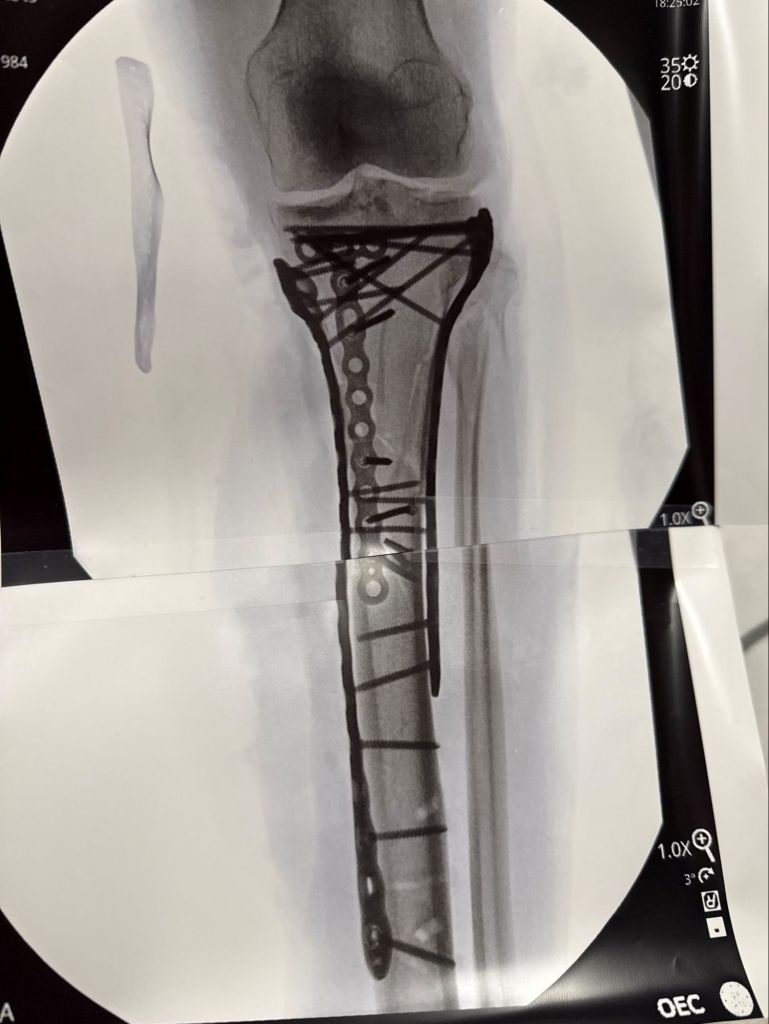

Lindsey Vonn, the Olympic skier, has revealed a photo of her broken leg after a serious crash at the 2026 Winter Olympics. She shared an x-ray image showing her broken bone stabilized with plates and screws.

Following the crash, Vonn had to undergo multiple surgeries in Italy. She suffered a left tibia fracture during the downhill event on February 8 and was airlifted off the course in Cortina d'Ampezzo.